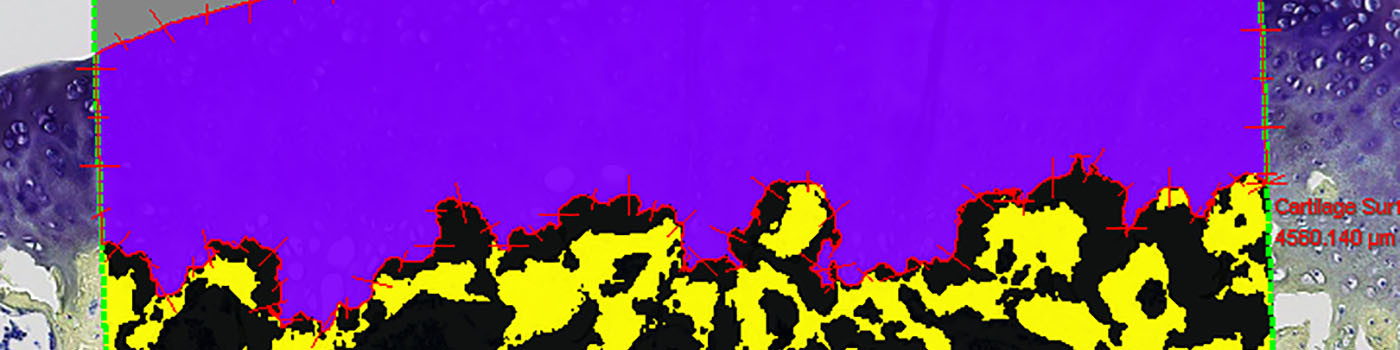

Figure 2

Close-up on tibia cartilage with Analysis box.

Figure 3

Tissue classified in cartilage, bone, bone lacunae, and joint space. Fibrillation Index measures marked as rulers on cartilage surface.